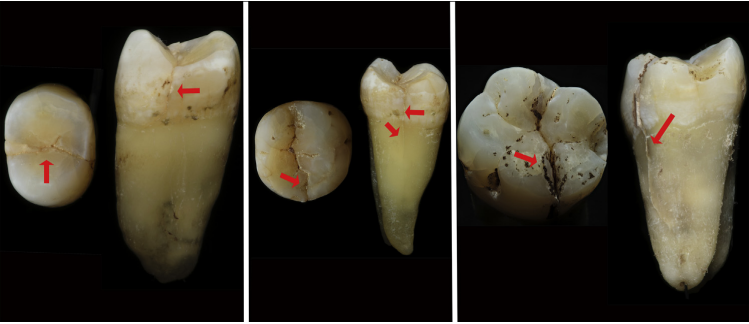

牙隱裂是指發(fā)生在牙冠表面的、不易被發(fā)現(xiàn)的細(xì)小裂紋,常不易被發(fā)現(xiàn)。這些裂紋可以深入到牙本質(zhì)結(jié)構(gòu),引起牙痛等一系列癥狀。牙隱裂具有隱匿性,診斷難,確診后療效不確定。

2. 口腔檢查時,醫(yī)生可能會使用探針、染色劑等工具輔助檢查,以確定裂紋的位置和深度。